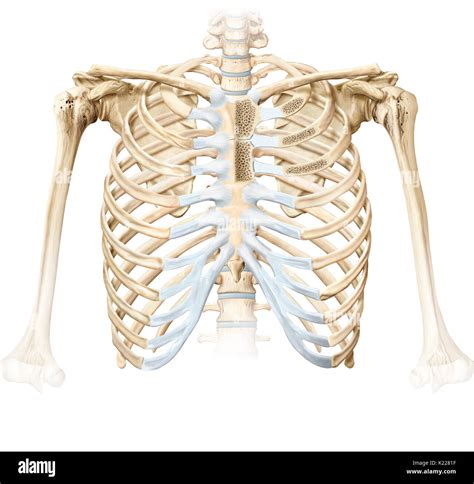

Anatomy of the Sternal Costal Joints

The sternal costal joints are classified into two types based on their location and structure:

• Sternal Costal Joints of the True Ribs (Ribs 1-7): These joints connect the true ribs directly to the sternum via costal cartilages. The costal cartilages of the true ribs articulate with the sternum at specific points, providing a stable connection.

• Sternal Costal Joints of the False Ribs (Ribs 8-10): These joints connect the false ribs to the costal cartilages of the ribs above them, which then articulate with the sternum. This indirect connection allows for more flexibility in the lower thoracic region.

The costal cartilages of the true ribs articulate with the sternum at specific points, providing a stable connection. The costal cartilages of the false ribs articulate with the costal cartilages of the ribs above them, which then articulate with the sternum. This indirect connection allows for more flexibility in the lower thoracic region.